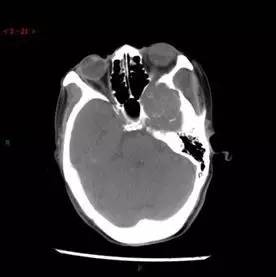

CT平扫轴位

解析:本病例为中颅窝至颞下窝沟通性病变,对周围骨质主要呈膨胀压迫性改变,伴囊变、出血。